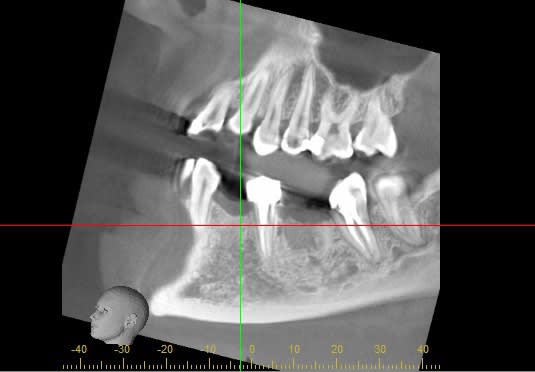

Il y a eu une extraction de 34 il y a 2 ans, et une extraction très délabrante sans comblement osseux, suite à abcès sur la 36, il y a un an.

--- Pour la 36 :

Malgré la temporisation de un an, je trouve que la densité osseuse semble anormal au niveau du site d'extraction.

Vous qui avez plus de recul, pensez vous qu'il s'agit d'un os cicatrisé, juste moins dense, ou alors de vraies lacunes osseuses ?

Dans ce cas, moi qui pensait poser un 5x10mm, pensez vous que je doive envisager une greffe de comblement par biooss et membrane pendant la chirurgie, ou bien ouvrir, mettre l'os et la membrane et refermer pour attendre encore, ou bien que la pose de l'implant sera possible, sans os.

En 36 tu n'as pas d'os, c'est du tissu mou et tu ne pourras pas stabiliser ton implant car proximité du NDI en apical( j'ignore combien tu as de marge). Avant de tenter les implantations tu devrais vérifier par un lambeau d'exploration c'est plus raisonnable.

Avec un cone beam tu n’a pas la densité osseuse exacte et selon la machine utilisé la vision du volume et de la qualité peut être fausse. Dans un premier temps tu peux modifier les réglages d’apparence en te basant sur le rendu d’opacité des racines, ton ressenti sur la zone à implanté pourrai être différent. Seulement au moment de la clinique tu aura la réponse.

Effectivement, la nullité du cone beam concernant la densité osseuse est très variable selon la machine utilisée. De simplement moyen à très mauvais, la discrimination entre les différents tissus dur est parfois difficile à établir, en tous cas le type d'os est parfois mal identifié. Tu peux parfois envisager un os correct et te retrouver dans la mélasse.

Bonjour Lounille, mon intension n’est pas que tu sois déçue de ton acquisition mais de te faire par uniquement des observations que j’ai pu faire des deux types d’acquisition d’un massif facial. Ces observations sont donc seulement celle d’un technicien spécialisé en modélisation 3D. Je vois une trame de structure différente au niveau du site d’extraction 36 que tu as pratiqué il y a 2 ans par rapport au reste du volume osseux. Généralement un cone beam me permet d’observer précisément cette trame mais ne m’indique pas la densité de cette partie alors qu’avec un scan cette information est clairement définie.